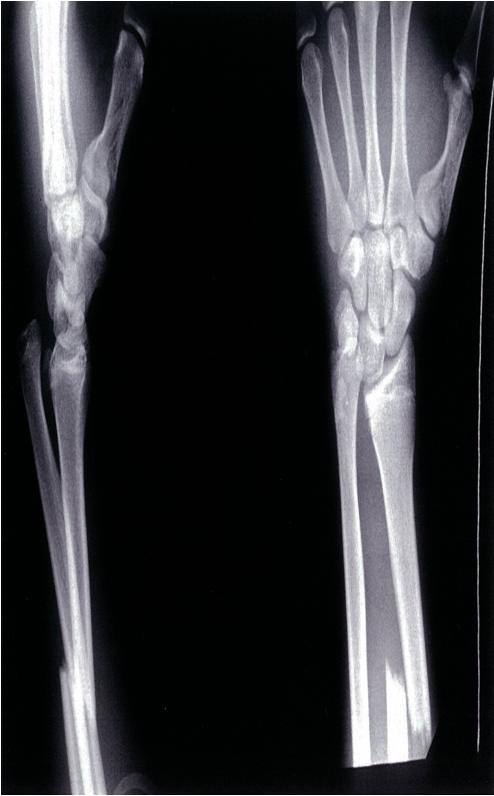

Shows a fracture at the mid to distal radial shaft, with subluxation or dislocation of the distal radioulnar joint (DRUJ)

Galeazzi fracture and fracture of the first metacarpal bone X-ray of the distal lower arm (left, lateral view; right, PA view) A distal third radius fracture and distal ulnar head dislocation can be seen; this fracture pattern is referred to as a Galeazzi fracture. Fracture of the first metacarpal bone